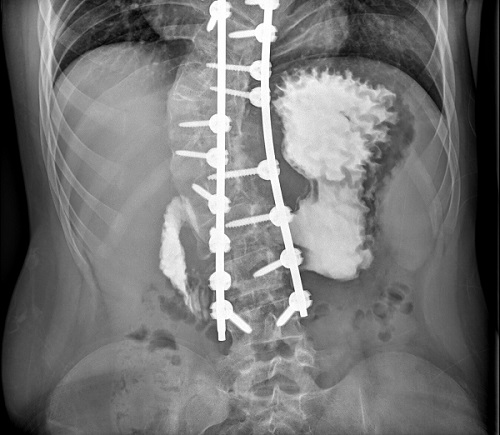

Se decidió manejo conservador con descompresión gástrica mediante sonda nasogástrica, dieta absoluta con sueroterapia intravenosa y reposición de las pérdidas con suero salino fisiológico. Tras 24 horas de ingreso se pudo pinzar la sonda sin presentar nuevos vómitos, por lo que se comenzó con tolerancia oral progresiva, que realizó de manera adecuada. Recibió el alta domiciliaria a los 5 días de ingreso. Precisó reingresar a los 3 días del alta por reaparición de la clínica, sin alteraciones metabólicas. Se completó estudio con angio-TC, pero los resultados no fueron totalmente valorables por el artefacto del material quirúrgico empleado. La evolución tras el reingreso fue satisfactoria. En los controles posteriores, el paciente se encontraba asintomático. Se le realizó un tránsito digestivo superior, donde se constató la normalización radiológica completa (Figura 2).

| Figura 2. Tránsito digestivo superior. Opacificación rápida del duodeno hasta su tercera porción, sin dilatación |